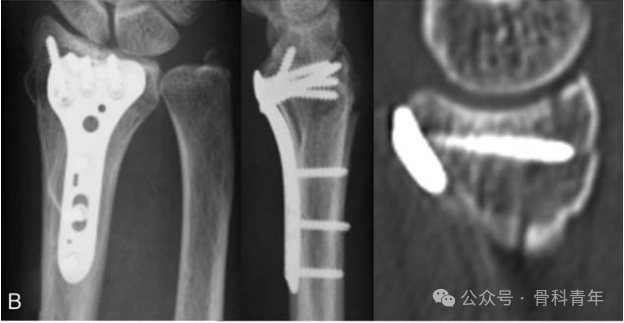

▲ 背侧组合式螺钉的固定方式,背侧螺钉方向取决于掌侧螺钉的方向,因此在方向上存在确定性,无法自由固定背侧骨块。